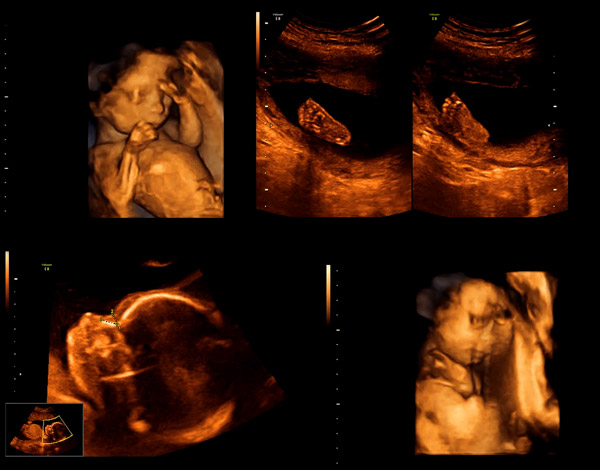

Gebelik dönemi boyunca düzenli takibin yapılması anne adayının daha sağlıklı ve güvenli bebek sahibi olmalarını sağlayacaktır. Gebelikte anomali taramasının önemi yani ayrıntılı ultrasonografi, gebeliğin 18-23. haftaları arasında yapılmaktadır. Bu taramada bebeğin organları ayrıntılı olarak görüntülenmektedir. Her kadın herhangi bir genetik ve yapısal sorunu olmayan bebeklere sahip olmak ister. Genellikle majör anomalili bebeklerin dünyaya gelme riski yüzde 3-5 civarındadır.

Anomali taraması, gebelikleri boyunca anne adaylarının yaptırması gereken en önemli tetkiklerden birisidir.Bu taramada amaç bebeğin organlarının ve gelişiminin sağlıklı olup olmadığını kontrol etmektir. Ultrason muayenesi yaklaşık olarak 30 dakika sürmektedir. Yapılan ayrıntılı ultrasonografide bebeğin; kalp odacıkları, kalp kapakçıkları, el ve ayak parmakları, kalp duvarları, midesi, bacak ve kolları, mesanesi, böbrekleri, damar giriş ve çıkışları, bağırsakları, yüz kemikleri, beyin ve beyincik gelişimi, karın duvarı, dudak ve burun anatomisi, beyin boşlukları, omurga sistemi, damak ve kulak gelişimi gibi tüm hayati organları detaylı bir şekilde değerlendirilir. Organlarda herhangi bir anomalininin olup olmadığına bakılır. Bebeğin organ ve sistemlerini bozan veya fiziksel olarak bebeğin görünümünü etkileyen her türlü bozukluk ve sakatlık fetal anomali tanımı kapsamına girmektedir.   gebelikte anomali taraması